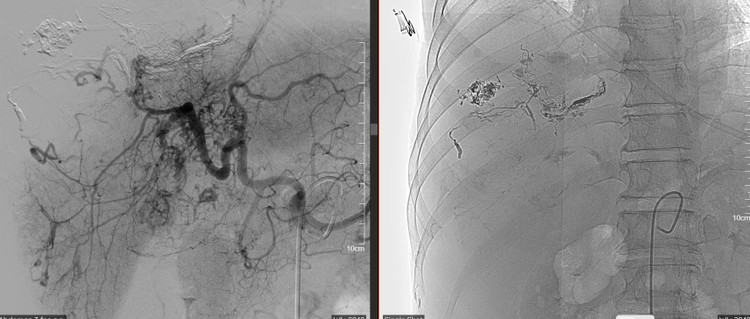

Kết quả chụp cắt lớp vi tính (CLVT) phát hiện khối u gan vỡ đang chảy máu hoạt động. Người bệnh được khẩn trương chuyển can thiệp chụp và nút mạch cầm máu cấp cứu.

Hình ảnh mạch máu cho thấy khối u lớn (kích thước ~10x11cm), tăng sinh mạch mạnh, nhánh phân thùy trước gan phải có dấu hiệu thoát thuốc cản quang – xác định điểm chảy máu chính.